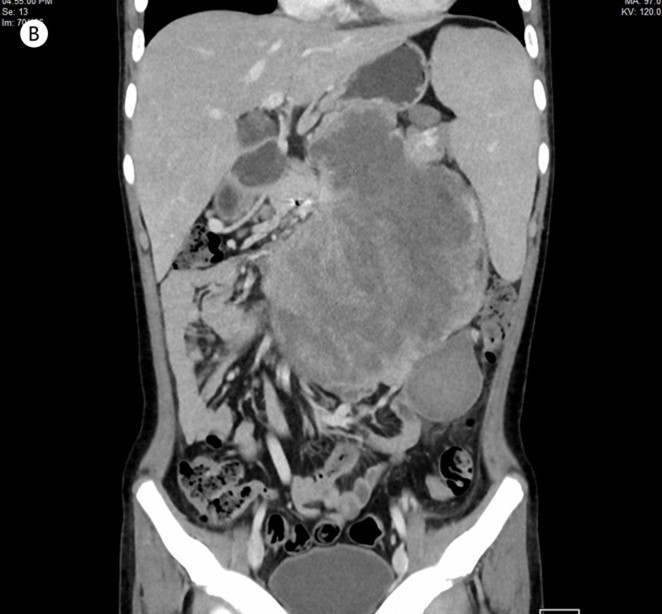

Retroperitoneal and Abdominal Sarcomas